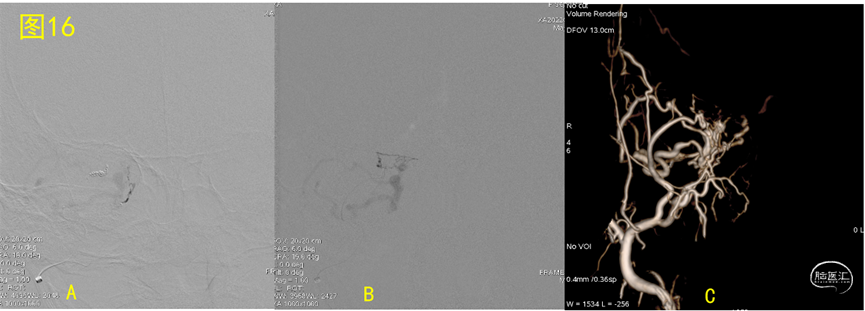

微导管到位,正位像Marathon (图16.A)和Echelon 10(图16.B)超选造影,后者解剖学结构更清晰,说明后者血流量大,选择 Echelon 10作为注胶主要途径, Marathon作为备选及补充注胶,图16.C为3D参考位置图